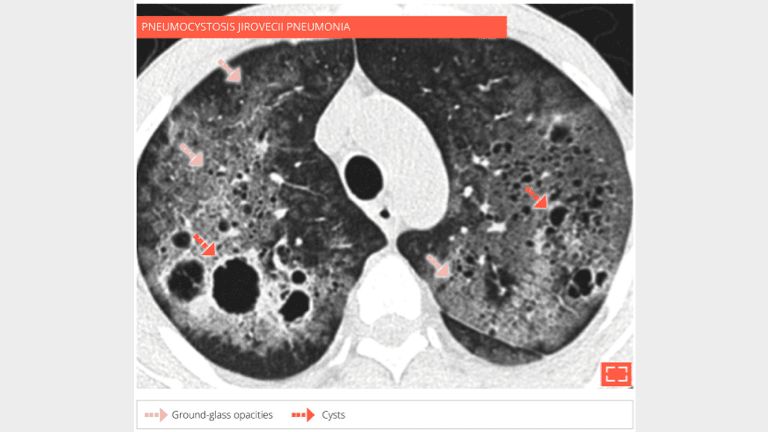

34-year-old man, HIV positive at AIDS stage. Progressive dyspnea for 1 month. The HRCT shows diffuse groundglass opacification with cysts of variable size. Diagnosis of pulmonary jirovecii pneumonia was done on bronchoalveolar lavage.